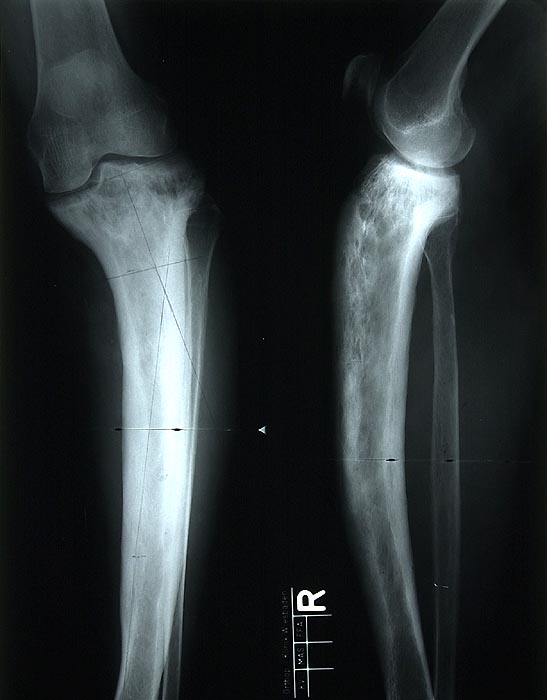

Morbus Paget

Knochen, Tibia

Im konventionellen Röntgenbild fällt eine grobsträhnig unscharfe und unregelmässig angeordnete Spongiosa auf sowie eine Verdickung der Kortikalis. Insgesamt ist der Knochen vergrössert. Aufgrund der verminderten Belastbarkeit hat sich die befallene Tibia nach ventral und lateral verbogen.